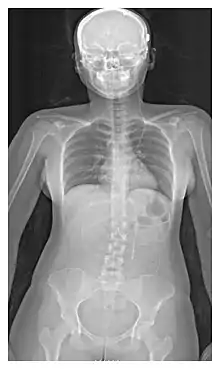

| Ventriculo-peritoneal shunt (VP shunt) | Peritoneal cavity |

| Ventriculo-atrial shunt (VA shunt) | Right atrium of the heart |

| Ventriculo-pleural shunt (VPL shunt) | Pleural cavity |

| Ventriculo-cisternal shunt (VC shunt) | Cisterna magna |

| Ventriculo-subgaleal shunt (SG shunt) | Subgaleal space |

| Lumbar-peritoneal shunt (LP shunt) | Peritoneal cavity |